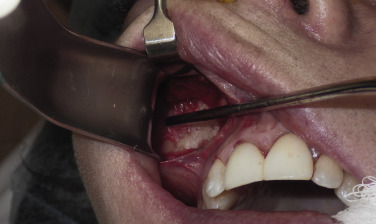

After the anterior maxilla is dissected, the periosteal elevator is angled, and the remainder of the dissection is primarily in an oblique vector ( Fig. 7.13 ). All of the common implants extend over the lateral maxilla and zygomatic regions and taper out to a thin tail. This oblique vector of dissection is carried out over the malar region and extends over the medial portion of the zygomatic arch. It is extremely important to remember that the implant pocket should be just slightly larger than the intended implant ( Fig. 7.14 ). A grossly larger pocket only serves to encourage mobility and dead space. This is even more important if screw fixation is not being used, so the smaller pocket will retain the implant and reduce mobility.